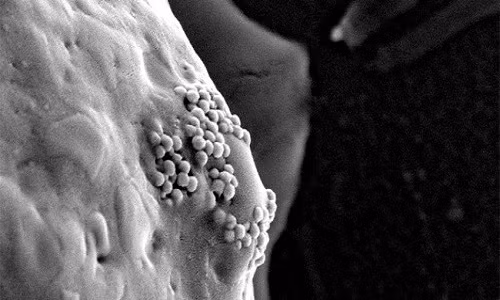

Các hạt nano vàng bám trên bề mặt tế bào ung thư. Ảnh: D. S. Wagner.

Khối u ung thư thường có các mạch máu rò rỉ. Khi hạt nano vàng được tiêm vào mạch máu, chúng có xu hướng thấm qua các lỗ mạch rò rỉ này và tụ xung quanh khối u. Những tế bào ung thư khi phát triển thường "nuốt" các hạt nano.

Nhóm nghiên cứu gắn hạt nano vàng vào các kháng thể protein miễn dịch. Kháng thể protein sẽ tiếp xúc với thụ thể trên bề mặt tế bào vảy, cho phép hạt nano vàng bám vào xung quanh các tế bào ung thư một cánh nhanh chóng.